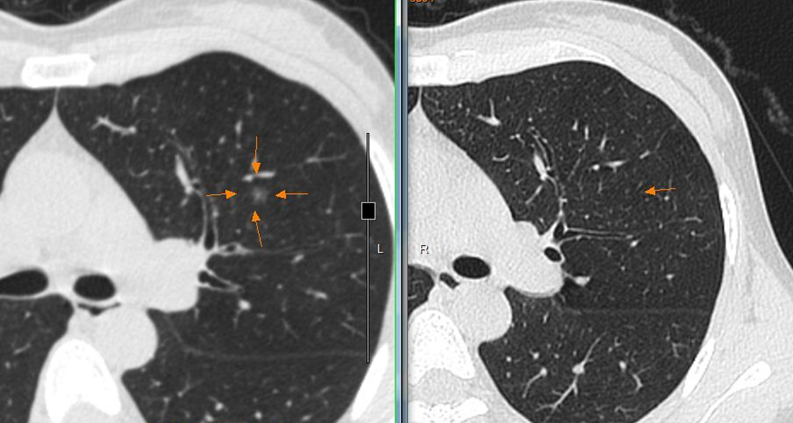

这是我前一段时间在门诊碰到的一名患者,经过门诊治疗后肺部结节消失了。